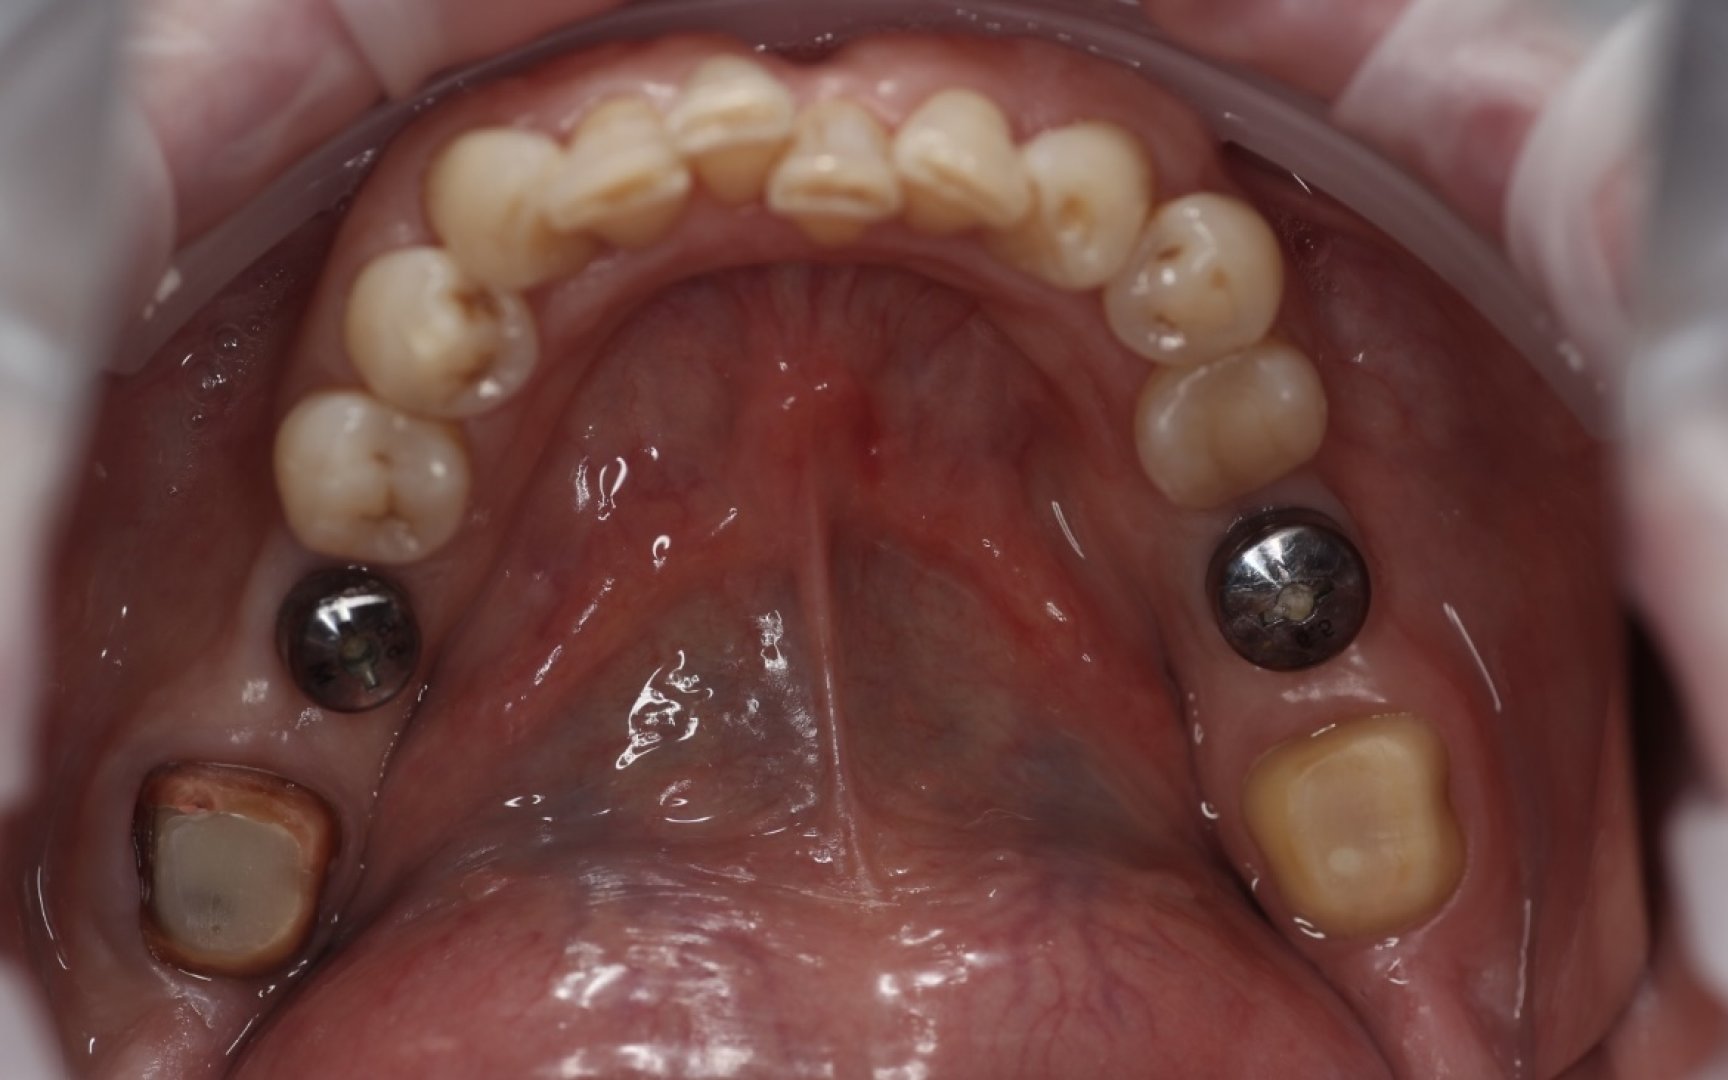

После установки формирователей десны и терапевтической подготовки 47 и 37 зубов, врачом-хирургом пациент Р. 45 лет был направлен для планирования дальнейшего протезирования жевательных зубов нч.

По плану лечения: дц коронки с опорой на ранее установленные интегрированные имплантаты Neodent 46 36, а также на зубы, укрепленные свш, 47 и 37.